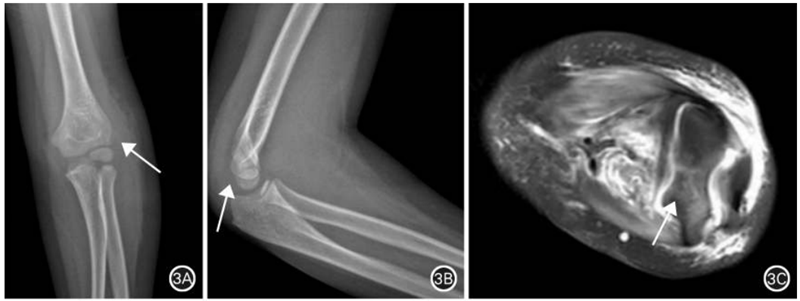

图3 肱骨外髁骨折。A.正位X线片示肱骨远端轻度移位撕脱骨折(箭头所示),关节软骨不可见;B.侧位X线片未见骨折块影;C.横轴位MRI示骨折累积部分关节软骨(箭头所示),损伤程度重于X线片表现